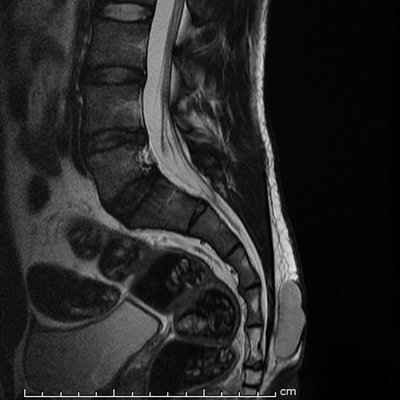

Dans la roneo 1 p3 je ne comprends pas pourquoi on dit que les cretes synostosiques sont visibles sur une radio de profil du sacrum. Pour moi elles sont visibles en vue antérieure et pas de profil.

5e82095e48779e72c4e6320dbe37f1.jpg

PS: En fait il faut raisonner en pensant radiologie ... Certes sur une vue latérale, toi, avec ton oeil, tu ne les verrai pas, mais à la radio, tu les vois !